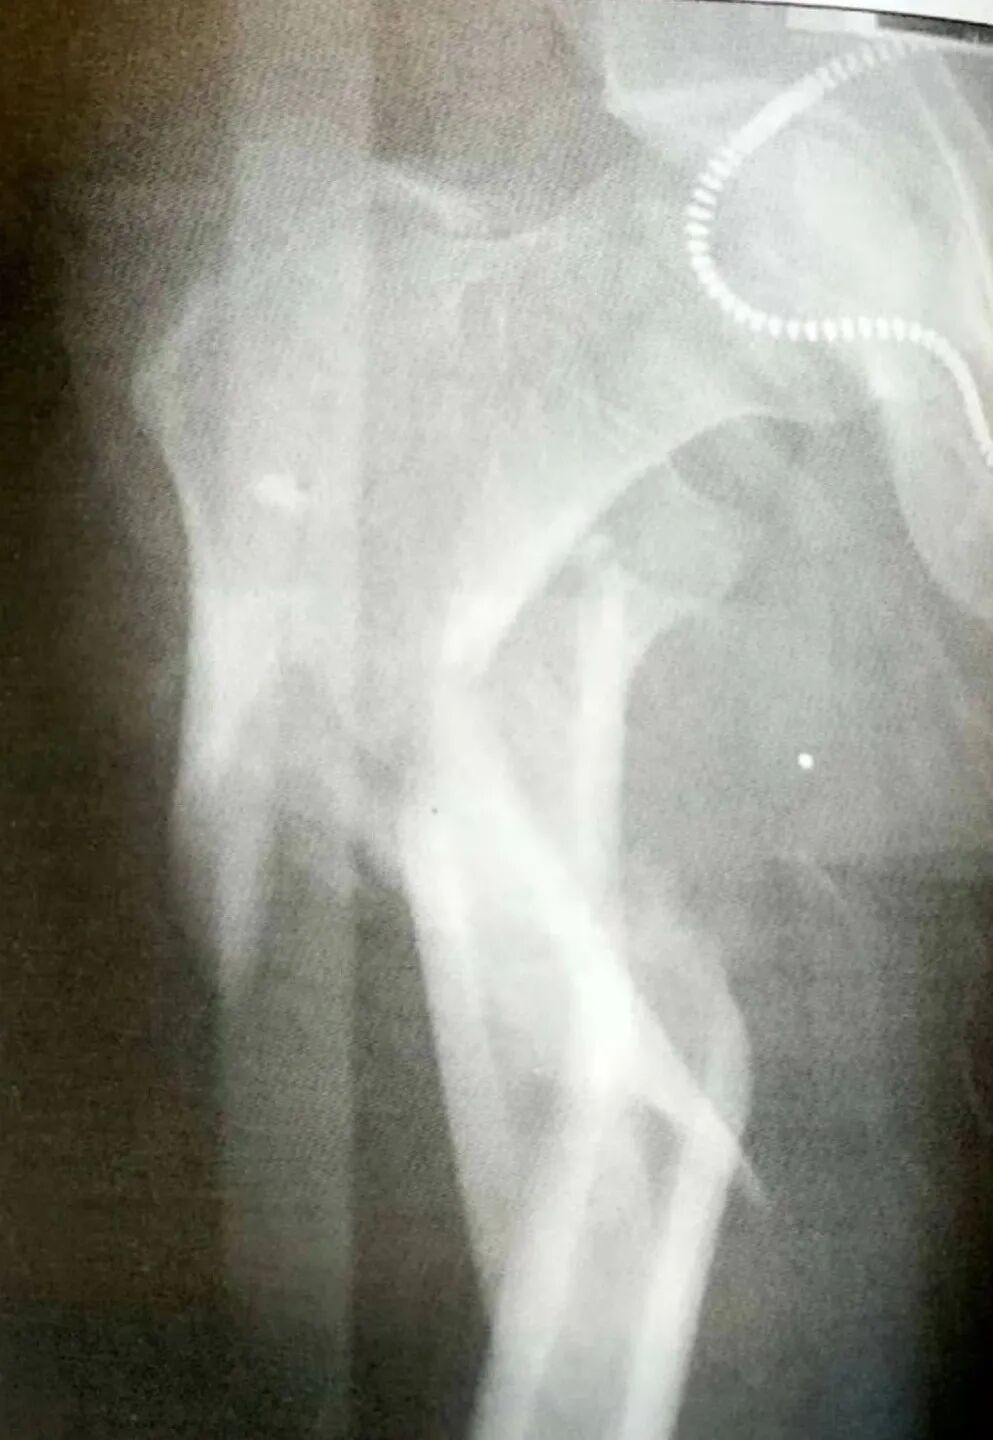

1)粉碎性转子下骨折

▲ 粉碎性转子下骨折